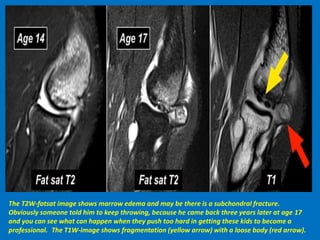

The T2W-fatsat image shows marrow edema and may be there is a subchondral fracture.

Obviously someone told him to keep throwing, because he came back three years later at age 17

and you can see what can happen when they push too hard in getting these kids to become a

professional. The T1W-image shows fragmentation (yellow arrow) with a loose body (red arrow).